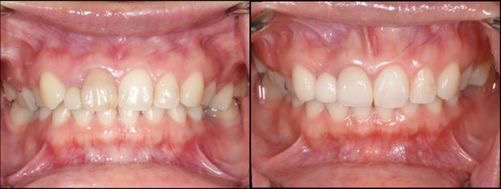

混合歯列から拡大装置を使用し、ワイヤーでの矯正に移行した症例。

天然歯を抜歯することなく、歯列不正を改善できた。

(左上は初診時、右上は拡大床セット時、左下は永久歯列に移行した時期、右下現在)